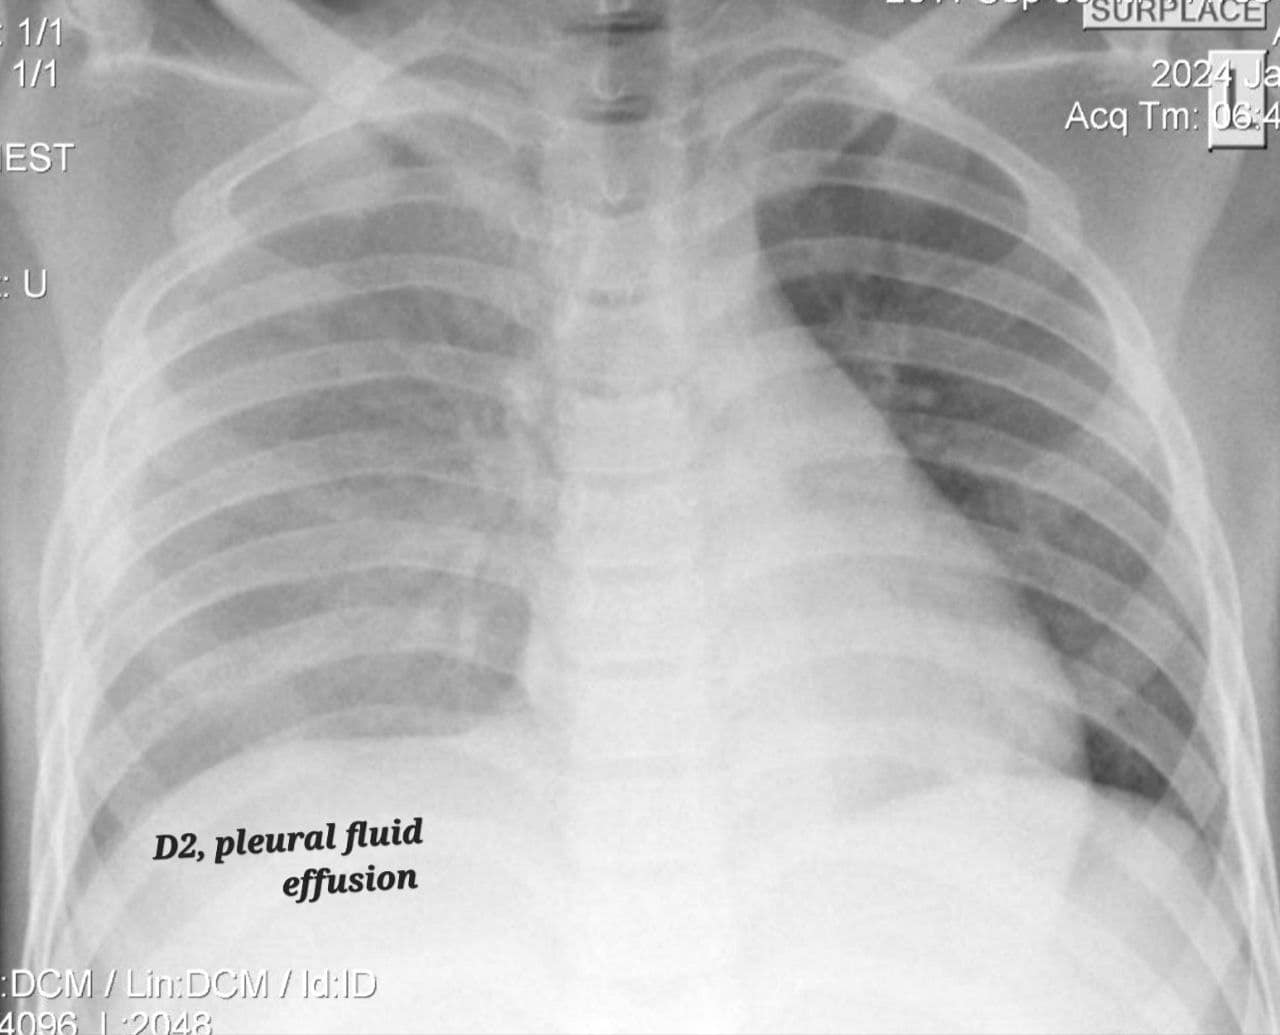

រាជធានីភ្នំពេញ៖ នៅថ្ងៃទី២៦ ខែមករា ឆ្នាំ២០២៤ យោងតាមការគណនីហ្វេសប៊ុកផ្ទាល់របស់ Dr. Beat Richner បានឱ្យដឹងថា​ ក្មេងប្រុសម្នាក់ អាយុ១២ឆ្នាំ ត្រូវបានព្យាបាលជំងឺគ្រុនឈាម បញ្ចូលសេរ៉ូមអស់៤លីត្រ មុខមកដល់មន្ទីរពេទ្យគន្ធបុប្ផា គាត់មានជំងឺគ្រុនឈាមកម្រិតធ្ងន់ធ្ងរស្មុគស្មាញបំផុត អស់ជីពចរ១៦ដង និង ចុងក្រោយសន្លប់បាត់ស្មារតី អស់រយៈពេល១៨ថ្ងៃ។

ក្មេងប្រុសនេះ ត្រូវបានសង្រ្គោះជីវិត ដោយប្រើឈាម-ប្លាស្មាអស់៦ប្លោក និងប្រើជំនួយម៉ាស៊ីនសប់ដង្ហើម ថែទាំព្យាបាលអស់រយៈពេល១៨ថ្ងៃ។ ថ្ងៃនេះ ក្មេងប្រុសមានជីវិតរស់ឡើងវិញ ដោយស្នាមញញឹម សូមអរគុណនិងកោតសរសើរដល់ក្រុមគ្រូពេទ្យឯកទេសសង្គ្រោះបន្ទាន់នៃមន្ទីរពេទ្យគន្ធបុប្ផាភ្នំពេញ ដែលបានសង្គ្រោះជីវិតមួយនេះ រាល់ការព្យាបាលទាំងអស់ គឺឥតគិតថ្លៃ សម្រាប់គ្រប់ៗគ្នា ដោយគ្មានការរើសអើង។